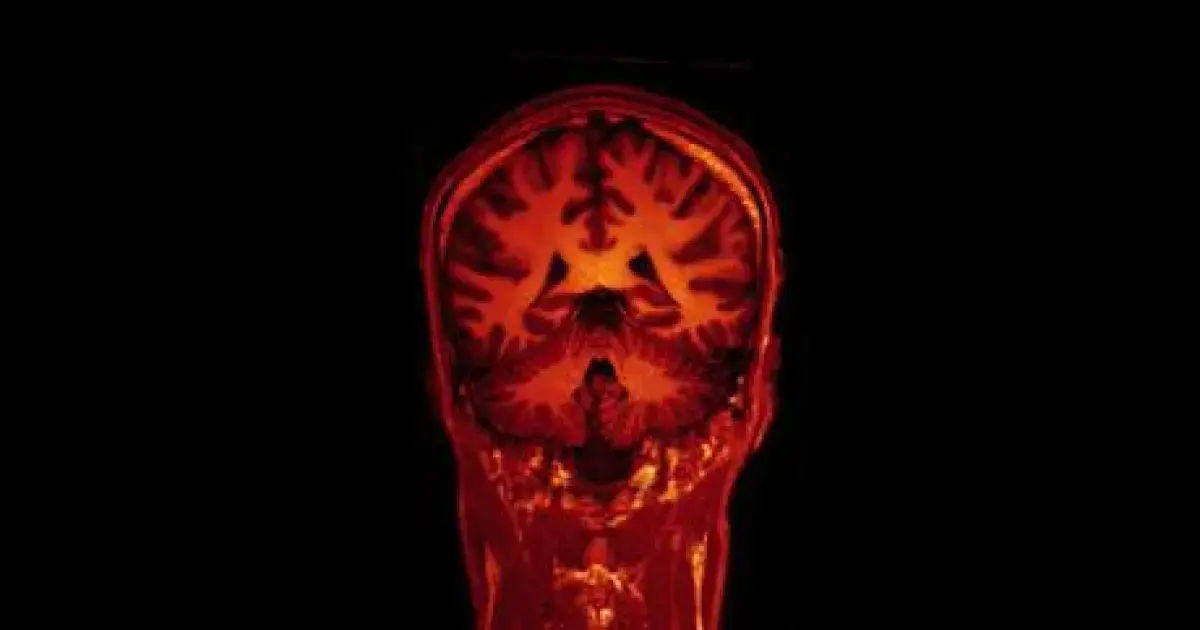

The team combined and analyzed data from 3,737 participants with normal cognitive functions, who were observed over several years. This included 10,343 MRI scans and 13,460 memory assessments.

“We now have the most detailed picture of how structural changes in the brain occur with age and how they relate to memory,” said Professor of Neurology Álvaro Pascual-Leone from the Marcus Institute for Aging Research at Harvard Medical School, the lead author of the study.

The findings were quite complex. The results did not pertain solely to the hippocampus—the area of the brain that plays a central role in memory and learning. The researchers found that memory decline was not linked to changes in any single area, as reported by Science Alert.

A reduction in brain tissue volume correlated with a decline in episodic memory, which is not surprising, but this connection was far from uniform. It became significantly more pronounced with age, especially in individuals over 60, and was most evident in participants whose brains shrank the fastest.